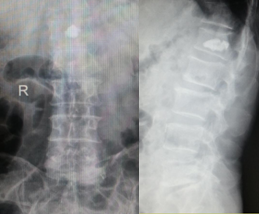

腰椎脫位切開(kāi)復(fù)位內(nèi)固定術(shù)